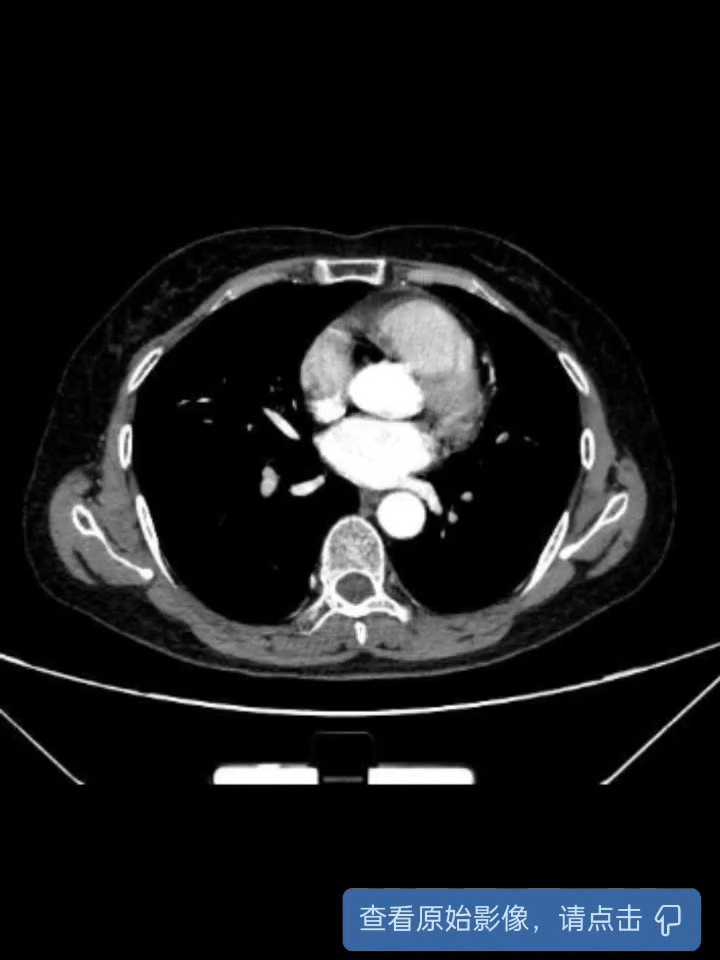

腹部增强CT